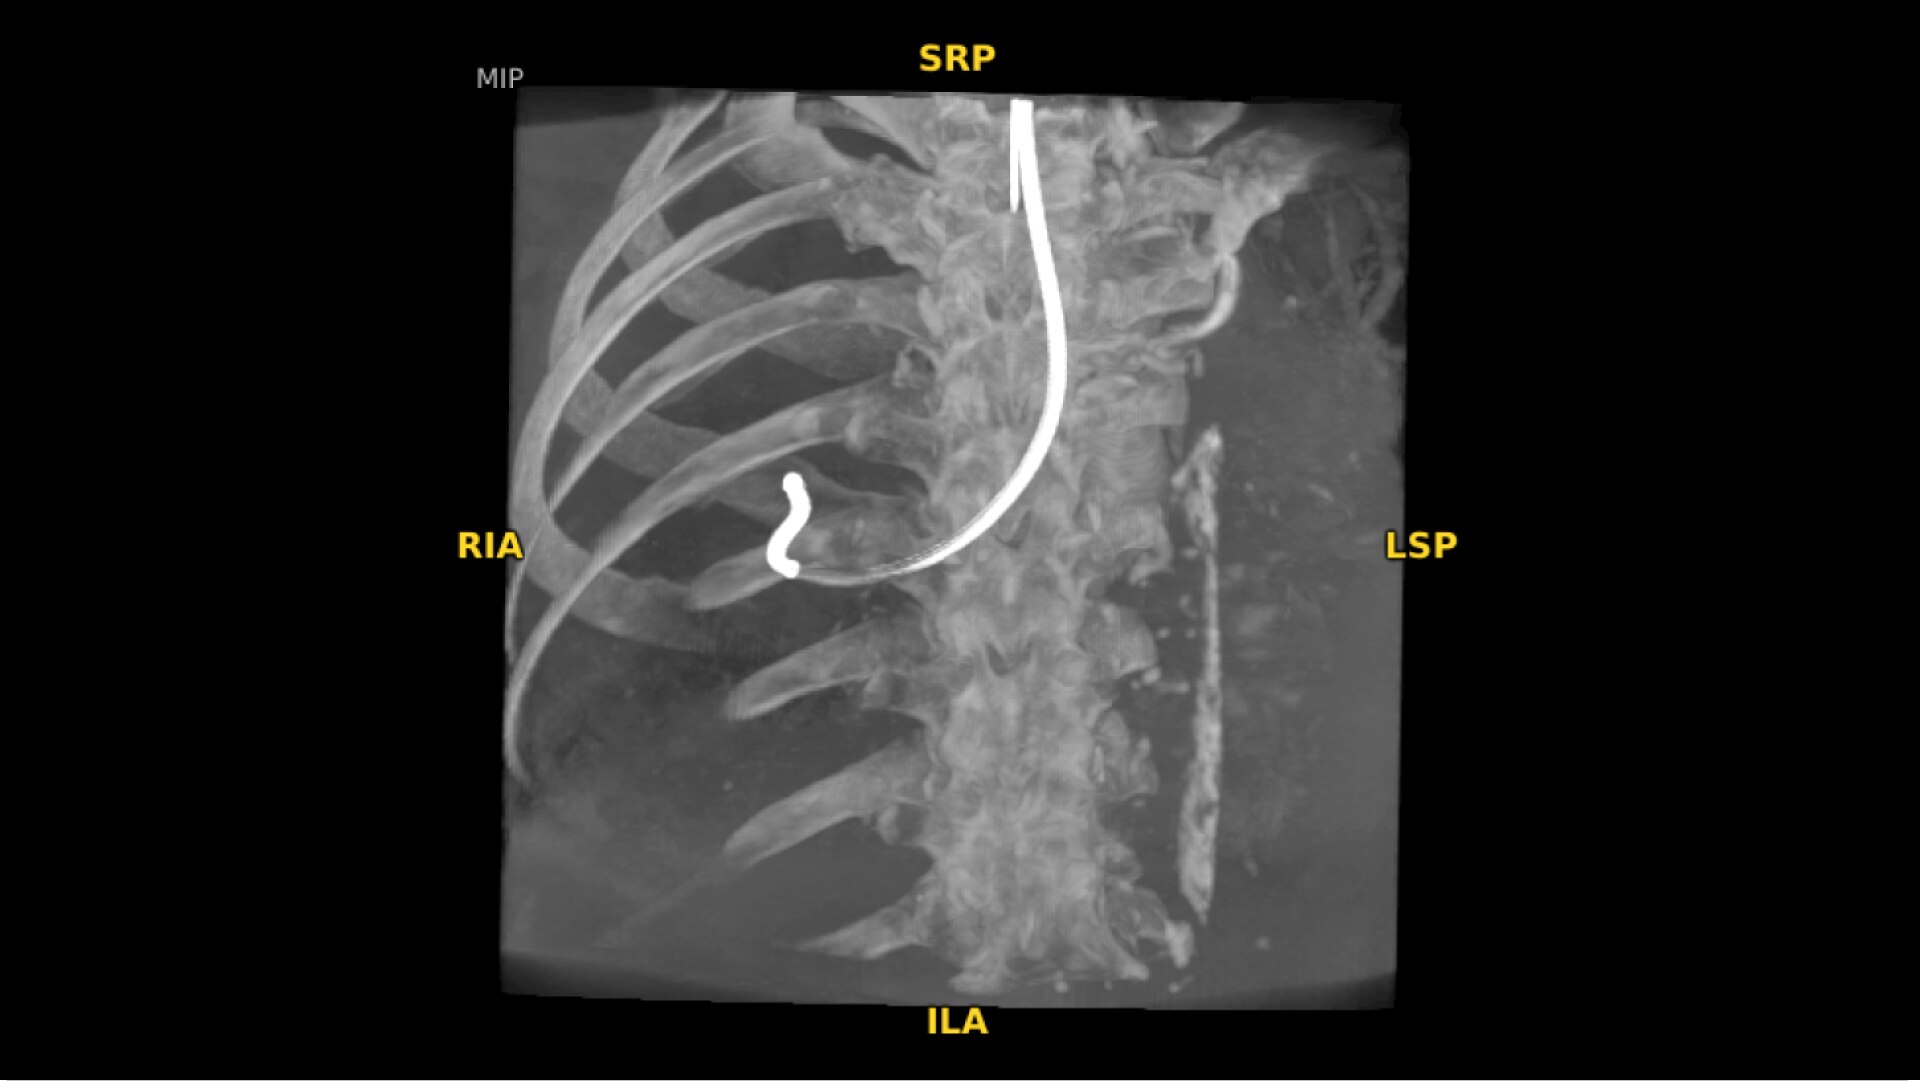

The OEC 3D provides comprehensive imaging with precise 19 cm x 19 cm x 19 cm 3D volumes and exceptional 2D images intraoperatively.

The OEC 3D presents five perspectives: Axial, Coronal, Sagittal, MIP, and VR, on a 4K display for clear and detailed review of 3D volumes and 2D images.

Augmented fluoroscopy aids visualization with ability to select point of interests in the OEC 3D CBCT volume and overlay on live fluoroscopy images. To accommodate patient and equipment positioning, the OEC 3D scan range is also adjustable for a simplified imaging workflow. Features available in Lung Suite application.